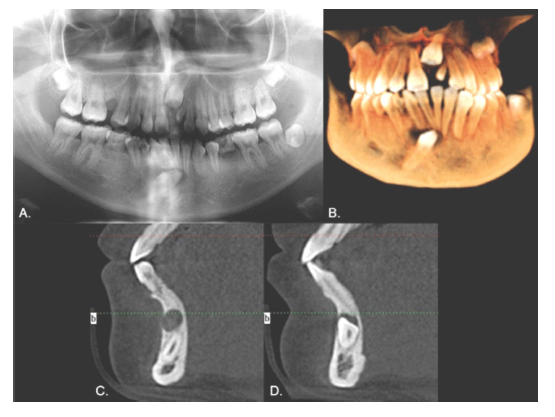

Male, 12 years old. Clinical examination revealed that the inferior left canine was the only primary tooth still present (Fig. 1). The panoramic radiograph showed that the 3.3 was in a type 1 transmigration (Fig. 2A). The cone beam computed tomography (CBCT) showed that the crown of the transmigrated canine was very close to the adjacent incisors’ roots (Figs. 2 B and C). Despite the recommendation for surgical removal or even orthodontic traction, the parents chose not to treat the transmigrated tooth and instead to follow up with periodic radiographs.

Female, 16 years of age. The 1.5, 2.1, 3.5, 4.3, and 4.5 teeth were missing, and the inferior right primary canine and two primary second molars were still present (Fig. 13). The radiograph showed that the 4.3 was in type 1 transmigration, the 1.5, 3.5, and 4.5 exhibited agenesis, and the 2.1 was impacted and had an associated supernumerary tooth (Fig. 14A). The simultaneous presence of supernumeraries and agenesis is a very rare (0.33%) condition known as concomitant hypo-hyperdontia (14). As in Case 6, the 4.3 was near the roots of neighboring teeth and the CBCT revealed a lesion that extended from the right deciduous canine to the left lateral incisor, almost as if showing the path that the transmigrated canine had followed (Fig. 14, B-D), so it was extracted. The 2.1 was surgically exposed and a post attached to it to allow its movement with orthodontics. The gap for the 1.5 was to be closed using orthodontics, but the spaces for the inferior premolars were to be maintained for later rehabilitation with dental implants (Fig. 15).